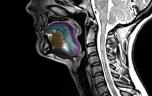

La sclérose latérale amyotrophique (SLA), également nommée maladie de Charcot, est une maladie neurodégénérative grave qui se caractérise par une atteinte des neurone moteurs (ou motoneurones), qui commandent, entre autres, la marche, la parole, la déglutition et la respiration. Cette perte des motoneurones entraîne une atrophie des muscles et une paralysie progressive conduisant au décès.

La maladie de Charcot est due à la mort progressive des motoneurones, les cellules nerveuses qui contrôlent les muscles volontaires qui gèrent la marche, la respiration, la parole. Les 2 types de motoneurones, centraux (situés dans le cerveau) et périphériques (dans le tronc cérébral et la moëlle épinière), sont touchés.